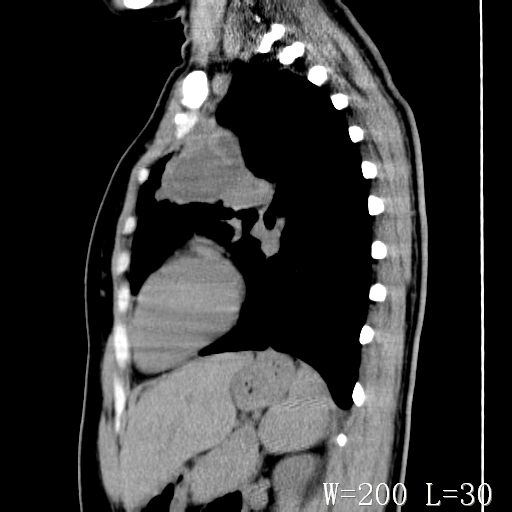

标题: CT27017:1、肺结核?2、永存左上腔静脉。 [打印本页]

标题: CT27017:1、肺结核?2、永存左上腔静脉。

女,32岁,自述肺结核治疗多年复查。

1)考虑左肺上叶肺脓肿,节段性肺不张。2)永存左上腔静脉。

1)考虑左肺上叶节段性肺不张。原因?2)永存左上腔静脉。

考虑左肺上叶胸腺瘤可能性大。肺不张/永存左上腔静脉

胸骨后偏左侧囊实性病灶,考虑胸腺瘤可能性大.

1、胸骨后偏左侧囊实性病灶,考虑胸腺瘤可能性大。2、永存左上腔静脉。